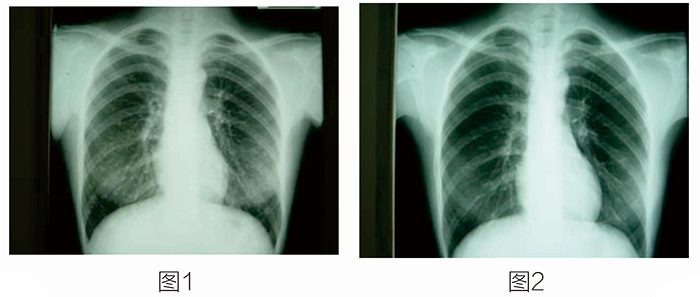

放射性核素治療開(kāi)展得最早、應(yīng)用得最廣泛的就是碘-131治療甲狀腺癌及其轉(zhuǎn)移灶,其它項(xiàng)目還有放射性核素治療癌癥骨轉(zhuǎn)移等。 這是一位34歲的女性,有甲狀腺乳頭狀腺癌。圖1示雙肺多發(fā)轉(zhuǎn)移。圖2是口服碘-131治療七次后,雙肺轉(zhuǎn)移灶完全消失。